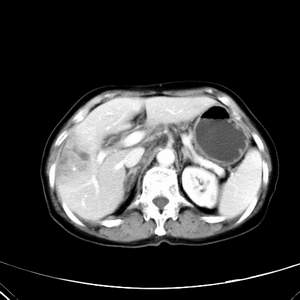

患者,女性,77岁,右上腹胀痛月余。afp正常。ca125升高。即往无肝炎病史。

肝右叶病灶是胆管细胞癌吗?门静脉右支癌栓形成?右侧肾上腺有问题吗?

最后5幅图片是延时7分钟的。门静脉右前支内有充缺吗?如有,肝血管瘤不好解释。

渐进性强化,中间见沙砾样钙化,首先考虑血管瘤

病灶渐进性向心性强化,延时病灶中心见条片状高密度影,局部见肝包膜回缩征,结合病人无肝炎病史,考虑肝右叶胆管细胞癌,门脉右支癌栓形成。